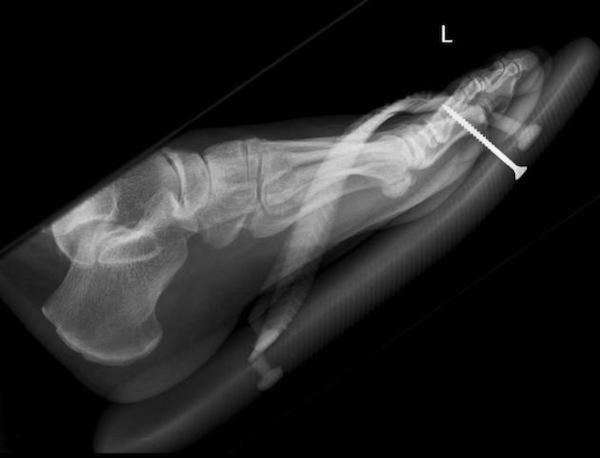

/ 15Wkręt

Wkręt czy gwóźdź w stopie to nic niezwykłego, ale rzadko tak głęboko.